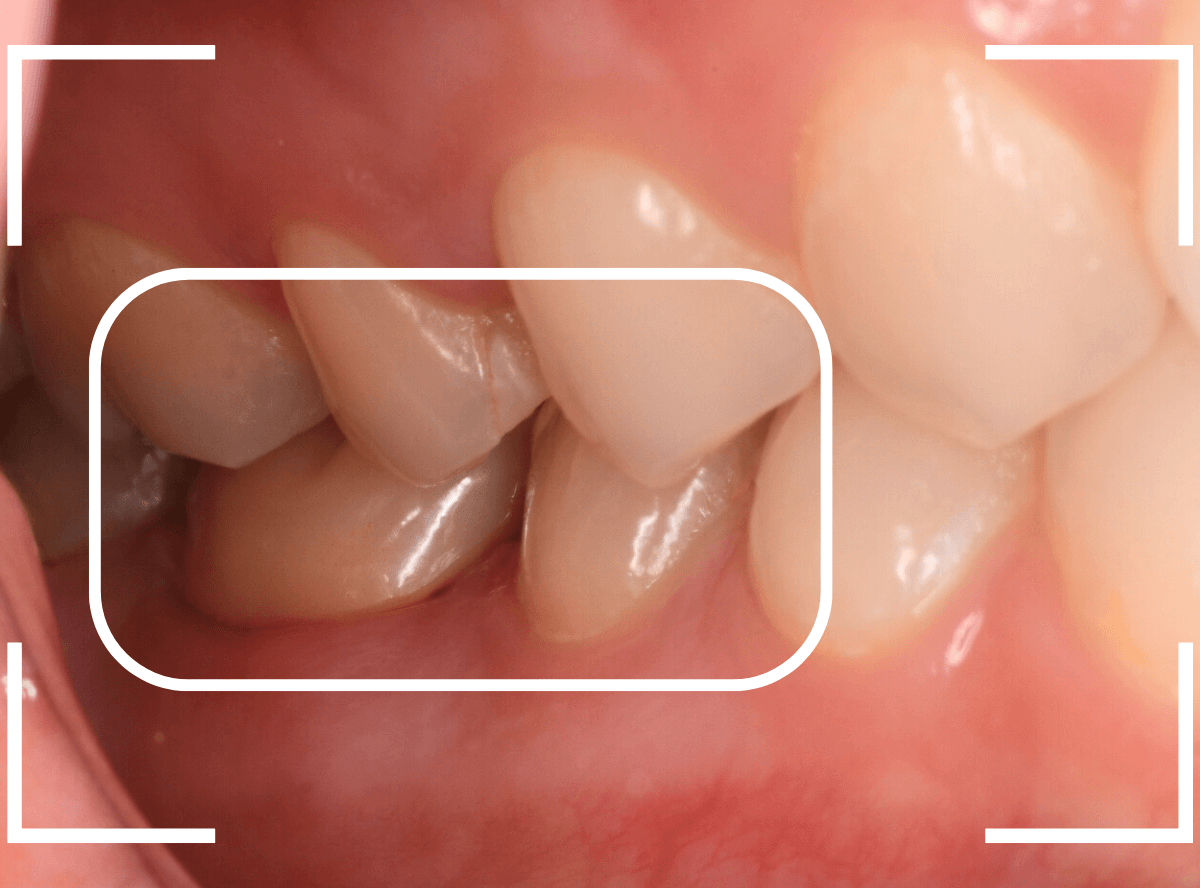

Case.7

治療中断の歯を、オール・ジルコニア・クラウンへ

歯の神経の治療後、土台まで作って長期間放置してしまった方です。

このような方は多く見受けられます。

ご本人には「痛くもないし、少し咬みづらい」くらいの感覚かもしれませんが、この状態で放置すると、歯はない方に動く習性がありますので、咬み合わせる反対の歯がずれてきてしまい、さし歯を作る際の支障になってしまいます。

この方も、反対の歯が大分ずれてきてしまいましたので、歯を大きく削る必要があり、調整に苦労しました。